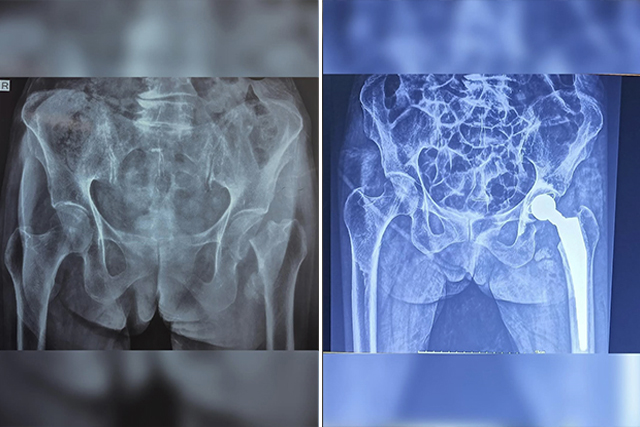

Total Hip Replacement